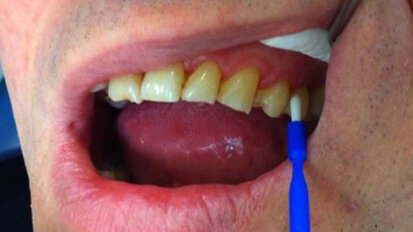

Il controllo chimico della placca nella terapia delle malattie parodontali e perimplantari placca-indotte

Le patologie infettive che colpiscono i tessuti parodontali e perimplantari hanno un comune primum movens eziopatogenetico: l’accumulo di placca ...